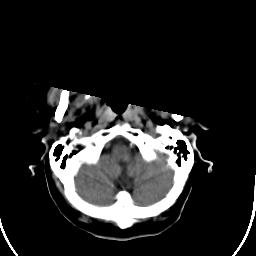

Stroke CT #1 -- Slice #2

[Home][Help][Clinical] Slice 2